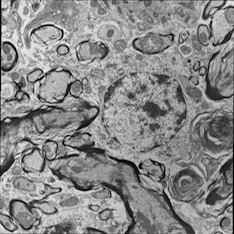

For image analogies based image registration, I have corresponding TEM/Confocal Microscopic image pairs of mouse brains with corresponding regions highlighted by a box. Using the correlative microscopy technique on the mouse brain, I want to localize specific brain regions associated with Pelizaeus-Merzbacher Disease (PMD) and do quantitative assessment of hypomyelination and demyelination in mice. PMD is one of a group of genetic disorders characterized by progressive degeneration of the white matter of the brain affecting the myelin sheath, the fatty covering that acts as an insulator on nerve fibers in the central nervous system.

The confocal microscopy images are multichannel color images in our test dataset. The blue channel is based on the blue stain DAPI (a fluorescent stain) which stains the DNA of the cell nucleus and corresponds to dark regions within the nuclei in the TEM. The green channel is based on the stains of the myelin sheats, visible as dark black layers covering the neurons in the TEM images. The red channel is not explicitly stained for and is caused by the auto-fluorescent effect of lipofuscin. The confocal image with RGB channels and its corresponding TEM image are shown in Fig. 5.

Currently I have six pairs of 2D TEM/confocal images with resolutions 582.24 pixels per μm𝜇𝑚\mu m and 7.5887.5887.588 pixels per μm𝜇𝑚\mu m respectively (1μm=1micron=106m1𝜇𝑚1𝑚𝑖𝑐𝑟𝑜𝑛superscript106𝑚1\,\mu m=1\,micron=10^{-6}\,m). The resolution is different between two images and only a small region in the confocal image corresponds to the TEM image.

From the example in Fig. 5, the blue and red channels are too noisy and contain less information compared to the green channel. We use only the green channel as grayscale image for the registration in our application. The datasets are roughly registered based on manually labeled landmarks with a similarity transformation model.

Refer to caption

(a) Red channel of confocal image

(b) Green channel of confocal image

(c) Blue channel of confocal image

(d) Grayscale of confocal image

(e) Confocal image

(f) TEM image

Figure 5: Example of Confocal image with RGB channels and TEM image